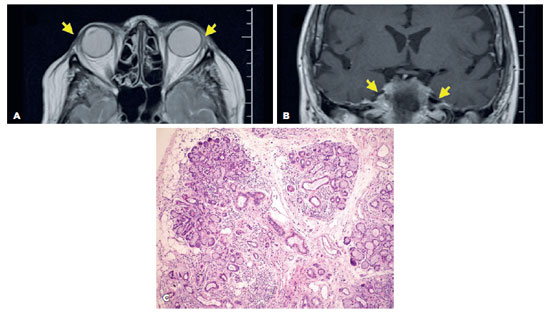

A 32-year-old white man presented with DES and dry mouth for 18 months. Prior to the visit, he received hydroxychloroquine sulfate, corticosteroids, topical cyclosporine, eyedrops, and punctual occlusion for presumed DES secondary to SS, without improvement. His only remarkable previous history was the use of AAS for bodybuilding, as follows: durateston (a solution of four molecules of synthetic testosterone, composed of propionate, fempropionate, isocaproate, and decanoate of testosterone at 30, 60, 60, and 100 mg of each compound per ml, respectively) at one intramuscular injection per week; and stanzonolol (100 mg) via intramuscular injection twice a week. Both were used, as mentioned above, for eight consecutive weeks, two months before the onset of symptoms. No other medications or diseases were reported. The ophthalmological examination demonstrated a visual acuity of 1.0 OU; a TFBUT of 8 s OU; no corneal fluorescein staining; and an ST of 40 mm OU. Examinations of MG and lid margins were normal, but the tarsal conjunctiva exhibited hyperemic and conjunctiva concretions (Figure 2). The OSDI was 90%, and the whole saliva flow was 0.20 ml/min. Serological tests for autoimmune and viral systemic diseases, including anti-Ro/SSA, anti-La/SSB, anti-dsDNA, anti-SM, anti-RNP, ANA, and rheumatoid factor, in addition to blood hormonal assays, were normal. A biopsy of his minor lip SG revealed a focus score of zero. The MRI evidenced that both LGs and the parotid SGs were absent (Figure 2A and B).

11-fig02tb.jpg)